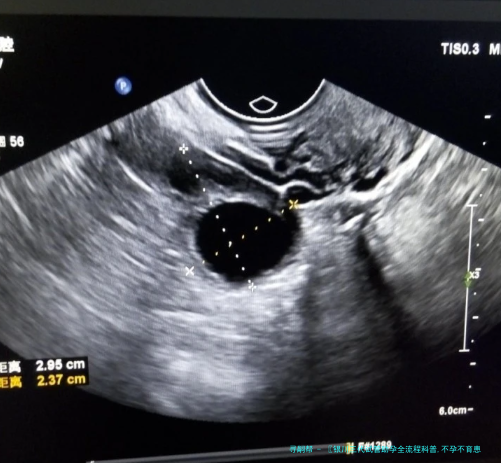

医生会陆续监测卵泡的大小和数量,认为最完美取卵时间。这个过程通常须要15-二十天,要求患者严格依照医嘱协同治疗。

取卵手术通常在静脉下进行,患者不会感应疼痛。医生在超声波引导下,用细针将卵子抽拿出来,全部过程安全可控。